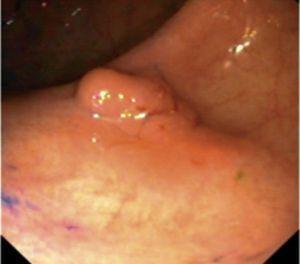

Fig. 4. Examples of protruding lesions with conventional examination and after the application of indigo carmine 0.2-0.5%. a, b) Sessile polyp. c, d) Subpedunculated polyp. e, f) Pedunculated polyp. g, h) Submucosal lesion (indigo carmine shows distinct innominate grooves, ruling out an epithelial lesion). i) Subpedunculated polyp. j) After indigo carmine application, a flat elevated lesion similar in size to the protruding segment is clarified.